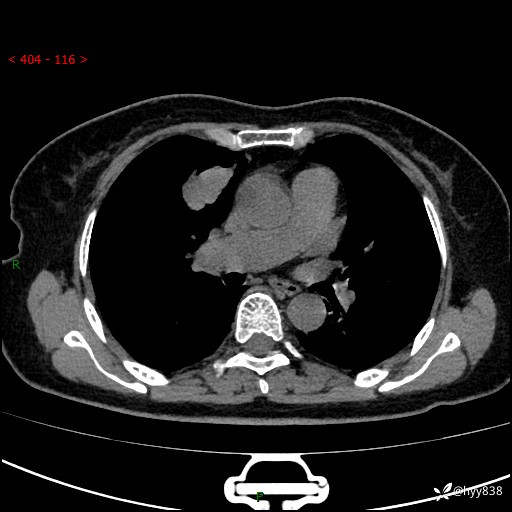

【患者信息】:70岁/女

【主诉】:发现右上肺肿物10天

【现病史及既往史】:者10天前因“背部酸痛”于当地治疗,无发热,无呕吐,无头痛头晕等不适,胸部CT示右上肺肿物。遂来我科就诊,门诊看过病人后以“”收入我科, 自患病以来,精神、饮食、睡眠尚可,大小便正常,体力体重无明显减轻。

【检查】:胸部CT平扫(患者过敏体质,不能增强)